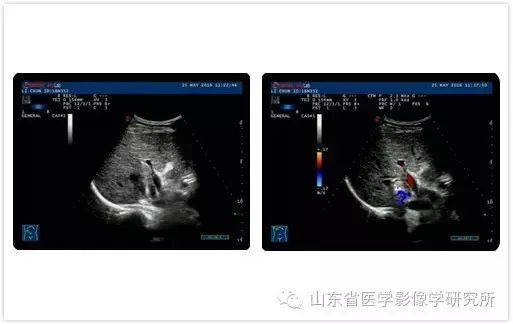

患者为41岁男性,因“乙肝病史10余年”到当地医院就诊。 腹部超声检查发现肝脏有肿块,与肝癌相符。 该病灶位于肝门附近,手术难度大且具有侵入性。 患者来我科就诊。 他不仅获得了肝细胞癌的病理诊断,还在超声引导下对肿瘤进行了彻底消融。 患者术后仅6小时即可下床活动,住院4天内顺利完成治疗。 。

▲术前超声检查

▲术前超声造影检查

▲术中

▲术后MR检查显示肿瘤完全消融